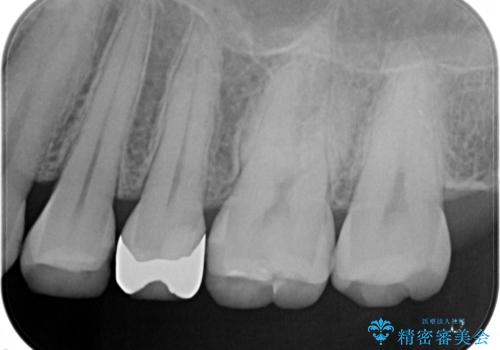

- 詰め物が取れたことを主訴に来院されました。

古い材料を除去すると中で虫歯が進行していたため、顕微鏡下で虫歯を除去した後セラミックインレー、PGAインレーにて修復治療を行いました。